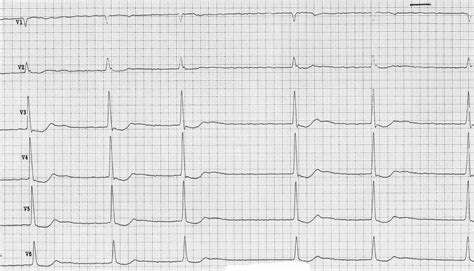

A belgyógyászati kivizsgálás részeként, különösen krónikus belgyógyászati probléma fennállása esetén, javasolt a szívgyógyászati (kardiológiai) és tüdőgyógyászati (pulmonológiai) szakvizsgálat, hiszen a szív és a tüdő a lehető legjobb állapotban kell, hogy legyen a műtét előtt. A várandósságot önmagában egy úgynevezett „stressz-tesztnek” is lehet nevezni, ami felszínre hozhat különféle megbetegedéseket. Ezek közül leggyakrabban a szív- és érrendszeri betegségekkel találkozhatunk (pl. magas vérnyomás, ritmuszavarok). Ilyen esetekben a várandósságot ajánlott előre megtervezni, és felvilágosítást kérni a lehetséges anyai, magzati vagy szülészeti szövődményekről. A várandóssághoz köthető rizikót az alapbetegség súlyossága határozza meg, de rendszeres követés mellett minimálisra csökkenthetők a lehetséges problémák. Mindezek és magasabb vérnyomásértékek esetén is ajánlott a kardiológiai szakvizsgálat.

A kardiológiai gondozás labor, EKG, szívultrahang vizsgálat, szükség esetén 24 órás EKG és/vagy vérnyomás monitorozásból áll a várandósság alatt. A terhesség előtti és utáni állapotfelmérést a terheléses EKG egészíti ki.